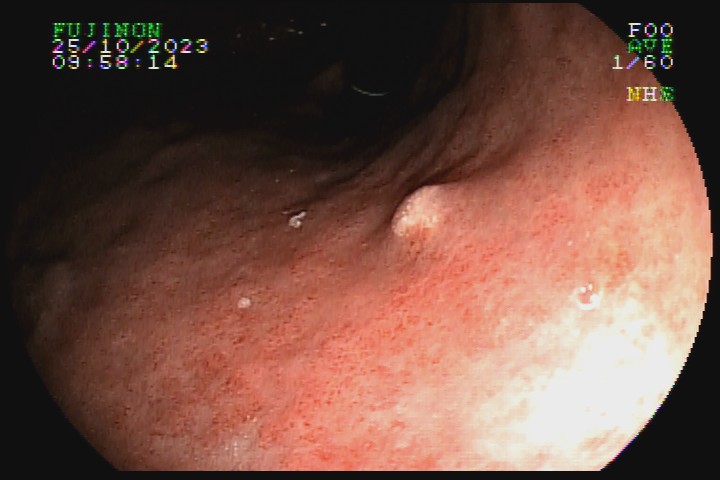

São depósitos de substâncias gordurosas, que podem estar associados a níveis elevados de colesterol sanguíneo. Possuem coloração amarelada ou esbranquiçada, aspecto polipoide ou plano, superfície rugosa, e geralmente são menores que 1cm.